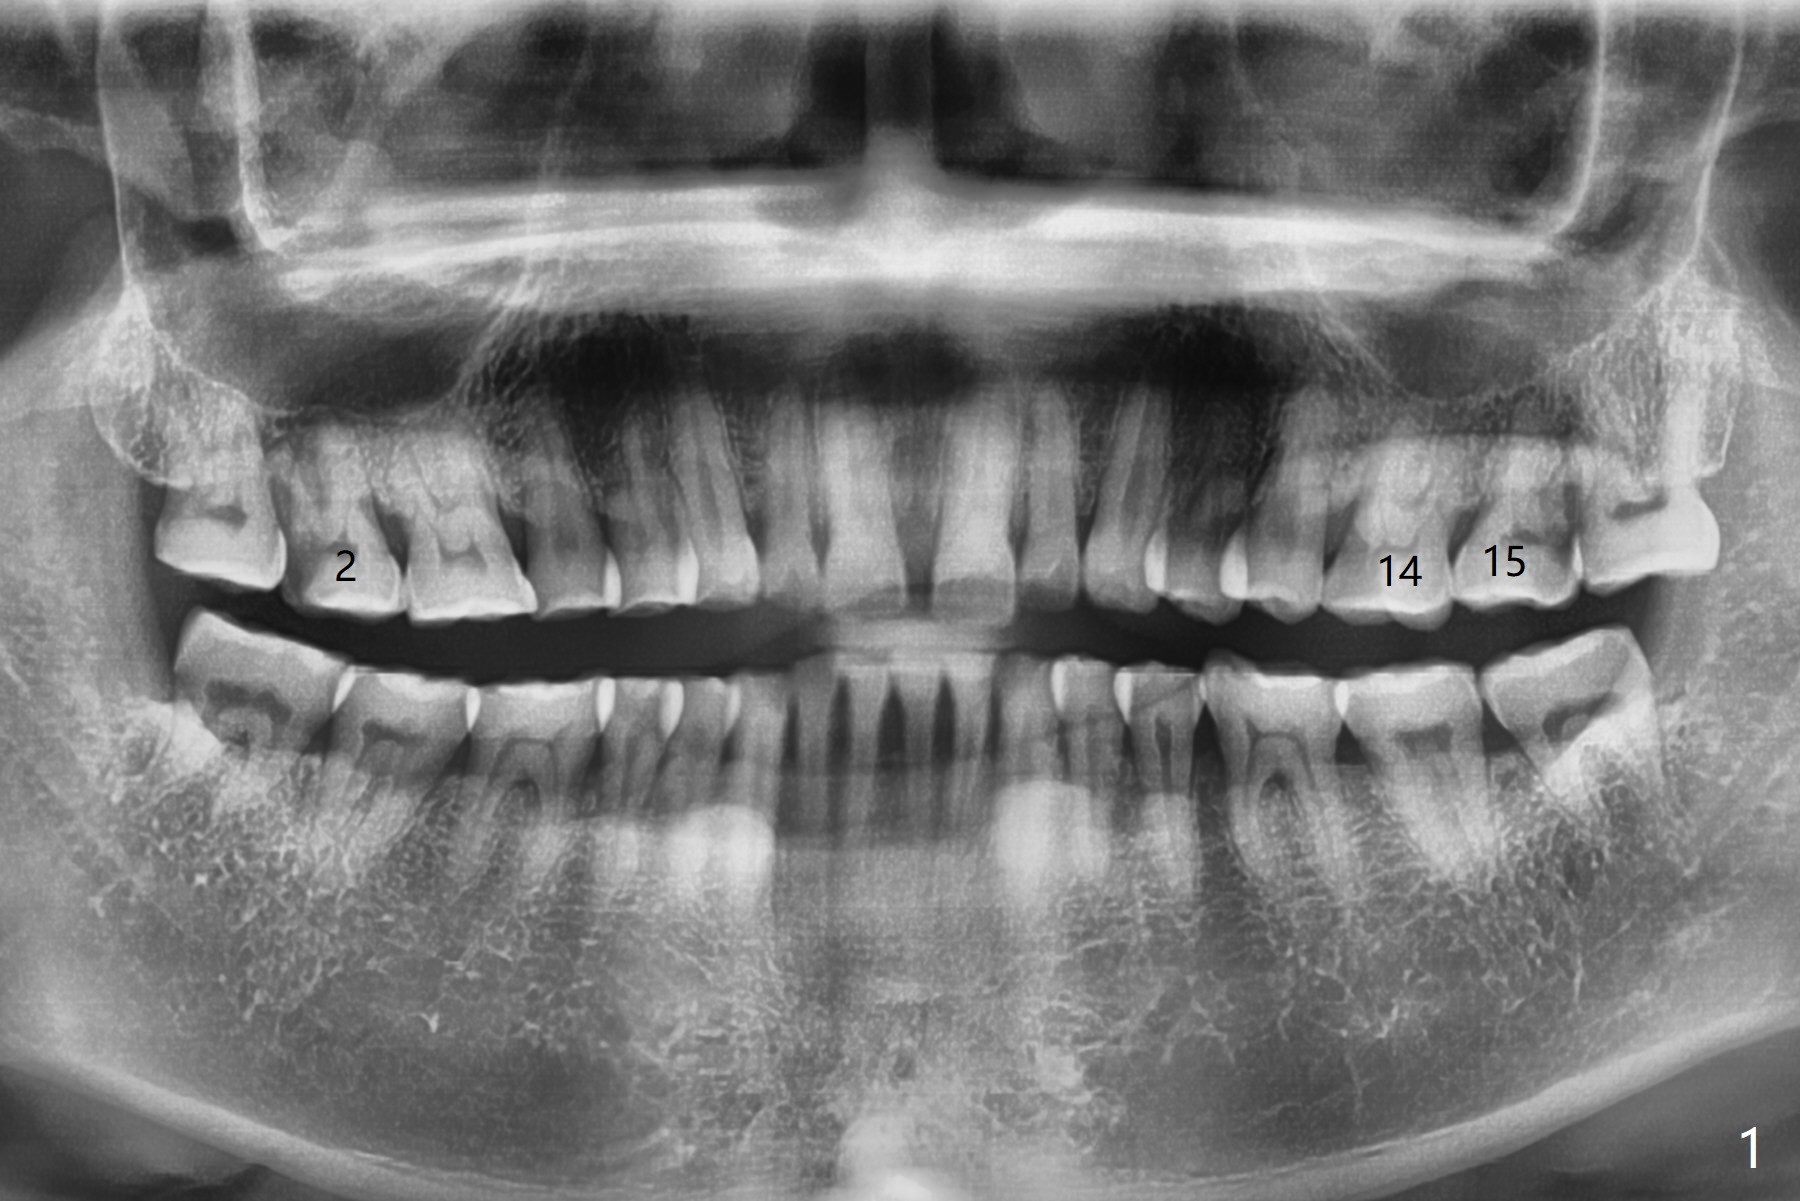

A 47-year-old man has pain at #2 and 15, while #14 has mesiolingual subgingival fracture (Fig.1). #2 is deemed non-salvageable by an endodontist, whereas RCT is finished at #15. When the patient returns for restoration, he reports that the filling is out at #15. In fact it has subcrestal fracture (Fig.2), while #14 equicrestal and difficult to restore (Fig.3). Although the patient agrees to have implants at #2 and 15, DB bone loss at #2 makes it difficult for implant (Fig.4). Use FC implant for primary stability. Insert a small piece of cotton pellet or healing screw and pack sticky bone around the implant before placing a temporary abutment. The latter will form a large gingival cuff, which makes it easy to place pair abutment without interference from the crestal bone. Screw loosening will be reduced. In fact there is PARL of the palatal root of #14 (Fig.5). A FC implant will be also placed at #15 for the same reason (Fig.6).